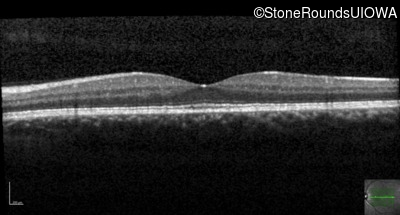

Optical Coherence Tomography - Right - 20/20 +1 sc

Exemplar / OCT Stack